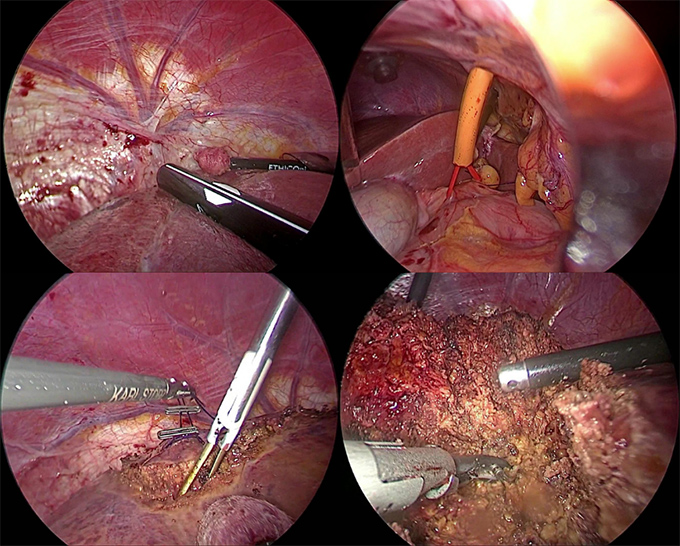

56歳女性。横行結腸癌同時性肝転移(肝S8)+傍大動脈リンパ節転移を認め当センターへ紹介となりました。B-mab+XELOX 3コース施行で著効を示し、PETでもnear CR(図1)となりました。腹腔鏡下肝部分切除術+右半結腸切除術を施行しました(図2−4)。手術時間は8時間25分、出血量は50g。術後14日目で退院となりました。原発巣、肝転移巣ともに病理学的CRでした。

術後の創部を供覧します(図5)。極めて高い整容性です。

図3 術中写真

病変部位や肝転移巣の画像